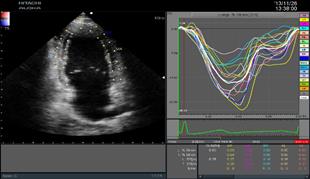

二維心肌組織追蹤2DTT

(2D Tissue Tracking)

ARIETTA 70-02模式匹配技術(shù)準(zhǔn)確識(shí)別并跟蹤感興趣的點(diǎn),智能化分析心肌節(jié)段運(yùn)動(dòng),準(zhǔn)確評(píng)估心肌局部運(yùn)動(dòng)功能及各節(jié)段運(yùn)動(dòng)的協(xié)調(diào)性,構(gòu)建左室“牛眼圖”,直觀顯示心室各段功能狀態(tài)。